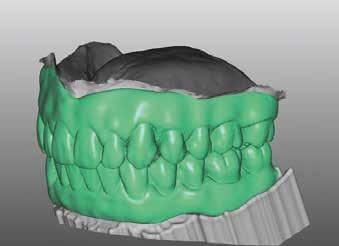

Terápia és implantáció

Az operatív beavatkozás előtt a behelyezett fogsorokkal és azok nélkül is beszkennelték az intraorális szituációt, valamint elkészítették a fogsorok digitális másolatát. Ezután óvatosan kihúzták a maradék fogakat, és mindent előkészítettek az azonnali implantációhoz, amelynek során 6 egyrészes SDS kerámiaimplantátumot terveztek behelyezni a meglévő alveolusba a 34-43 közötti területre. Közvetlenül a behelyezést megelőzően a szék mellett még egyszer megtisztították Diener Denta Plas plazmakészülékkel (lásd 49. kép) az implantátumokat, a lehető legteljesebb csírátlanítás – így a páciens csíraterhelésének minimalizálása – érdekében (2. kép) Az alveolus ózonos tisztítását követően behelyezték a hat egyrészes SDS kerámia-implantátumot, A-PRF (saját vérlemezkében gazdag – a ford.) membránokkal megsegítve. A laborkészítésű előre mintázott elemek alapján azonnali ide-

iglenes került az implantátumokra (3. kép), majd röntgennel újólag ellenőrizték a létrejött helyzetet (4. kép)

Arcszkennelés a fogpótlás készítéséhez

A megfelelő, 3,5 hónapos gyógyulási fázist követően, az implantátumok környezete tökéletes, irritációmentes képet mutatott (5–6. képek). A szituációt így intraorálisan be lehetett olvasni, digitalizálni, majd ezen adatállománnyal a pácienst elküldhették Norbert Wichnalek laboratóriumába. A harapást a régi fogsorok segítségével rögzítették, majd arcszkennelés és virtuális digitális lenyomatvétel következett. A páciens gyakorlatilag virtuálisan minden porcikájával ott volt a laborban. Első lépésben következett az így időben